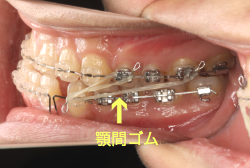

今回の患者様の場合は、「外科」も「小臼歯抜歯」も拒否されましたので、歯科矯正用アンカースクリュー(以下 アンカースクリュー)を用いて、下顎の歯列全体を後方に下げるという方法を取りました。

治療中の写真で、アンカースクリューより歯を後ろへ牽引しているのがお分かりいただけるかと思います。牽引を1年ほど続け、途中補助的に上下にゴムをかける(これを顎間ゴムと言います)手法なども追加し、全体で21ヶ月で治療を終えることが出来ました。

結局歯の本数を減らすことなく、すべてご自分の歯を残して、正しい配列と噛み合わせにすることができました。凸凹があまりひどくないため、簡単そうに見えると思いますが、このケースの初診の状態を見ると、熟練の矯正歯科医でも悩みのつきないケースです。まして、外科も出来ない、抜歯もイヤ、と言うことになると、従来の方法では治療不可能と考えられるのですが、アンカースクリューを使うことで最近は不可能が可能となってきました。